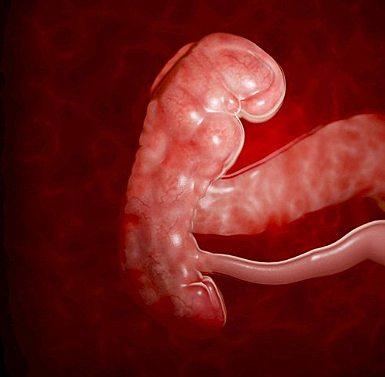

En la 6 semana del embarazo ocurren cambios.El embrión ya mide entre 2 y 4 milímetros en la 6 semana de embarazo. Este es el comienzo del periodo embrionario, se produce la formación de la mayoría de los órganos y en este momento es que se forman las malformaciones

En esta semana a la mujer le ocurren cambios y también ya se a desarrollado un poco el feto en la séptima semana de gestación. El embrión tiene 5 semanas de vida y mide aproximadamente 1,3 centímetros. La mujer puedes sentir frecuentemente deseos de orinar. Es normal porque el útero empieza a ejercer presión sobre la vejiga.

El embrión mide aproximadamente 13 mm desde la punta de la cabeza hasta las nalgas.Comienza en su cabeza a formarse y perfilarse las orejas , los ojos y donde empieza a formarse la punta de la nariz, la cabeza es todavía muy grande en comparación con el resto del cuerpo. Por eso, aunque su columna vaya enderezándose poco a poco, la cabeza todavía permanece hacia delante. También comienza a borrarse la columna del embrión y comienza a formarse los cuatro huesos unidos los cuales forman el coxis.

En la 9 semana del embarazo tu bebé,que en este momento se conoce como feto, ahora que la cola del embrión ha desaparecido,en esta semana ya comienza a estirarse y enderezar su tronco y este bebe mide cerca de 2,5cm de largo.